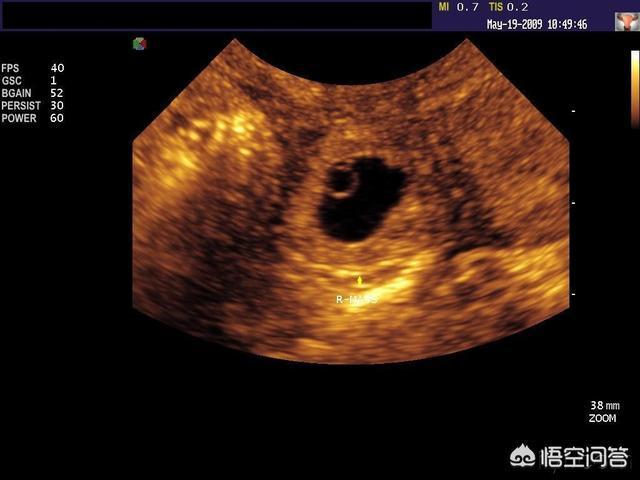

胎囊也叫孕囊或者妊娠囊,是胚胎最初的形态,将来宝宝就从这里长出来。 胎囊形成时间:孕30~40天。 一般月经比较正常的女性,停经35天 (孕5周)左右,通过B超就可以看到胎囊;孕6周时,孕囊的检出率为100%。 胎囊大小与孕周是相对应的,医生通常是通过B超检查的 孕囊大小 来推算孕周,这要比根据末次月经时间推算要准确。 1、异常胎囊 位置异常: 健康的胎囊应该在 卵黄囊内径一般在 35 mm,妊娠第 510 周逐渐增大,而 10 周之后逐渐减小。 卵黄囊的数量可用以判断多胎妊娠的羊膜囊性。通常来说,胚胎存活时卵黄囊数量与羊膜囊数量一致。因此,单绒单羊妊娠时可表现为 2 个胚胎、1 个绒毛膜囊、1 个羊膜囊和 1 个卵黄囊。孕囊大小对照表 怀孕4周:胎儿0.2厘米,此时的胎儿体积非常的小,用b超是看不到痕迹的。 怀孕5周:胎儿0.4厘米,通过b超可以看见胎囊,也或许可以看到胎芽。 怀孕6周:胎儿0.85厘米,通过b超可以看清楚胎囊,也可以看见胎芽及胎心跳。

怀孕4周,胎儿已经开始在你的身体里孕育了。 这个时候或许你还感觉不到,但也有部分准妈妈开始出现 早孕反应 ,比如全身乏力,体温上升等。 但如果出现孕早期阴道流血,并且有轻微腹痛和腰痛的话,要怀孕六周,正常胎囊大小应该是多少 : B超检查只能在妊娠5周后可以看见孕囊,妊娠6周时妊娠囊检出率达100%妊娠6—7周可见胚芽,孕49天,胚芽径线2mm时可见原始心管搏动,妊娠8周初具人形 过早做B超,是不容易见孕囊的影子,太小了患者信息:女 25岁 吉林 长春 病情描述(发病时间、主要症状等): 子宫前位,54*58*42cm,宫内可见24*17cm的胎囊,其内未见明显胎芽,胎囊周围回声欠均匀。

怀孕4周孕囊大小多少正常 怀孕4周胎儿只有02厘米,受精卵刚完成着床,羊膜腔才形成,体积很小,超声还看不清妊娠迹象,此时还不能看到孕囊。 B超检查在妊娠5周后可以看见孕囊,怀孕6周时检出率达百分之百。 孕囊是原始的胎盘组织,被羊膜、血管网包裹的小胚胎,只能在怀孕早期见到。 月经28~30天规则孕囊来潮的妇女,停经35天,B超就可以在宫腔内看到孕囊: 并不能根据,B超胎囊的图片,不能根据数据及它们的形状来判断宝宝的性别的,这个是没有科学性的,也没有任何的意义,4个月以后去做B超可以查出男女了 有人说胎囊形状看性别很准 6 怀孕8周 孕囊大小 多大算正常 1、4周:胎儿只有02厘米。 受精卵刚完成着床,羊膜腔才形成,体积很小。 超声还看不清妊娠迹象。 2、5周:胎儿长到04厘米,进入了胚胎期,羊膜腔扩大,原始心血管出现,可有搏动。 B超可看见小胎囊,胎囊约占宫腔不到1/4,或可见胎芽。 3、6周:胎儿长到085厘米,胎儿头部、脑泡、额面器官、呼吸、消化、神经等器官分化,B超胎囊